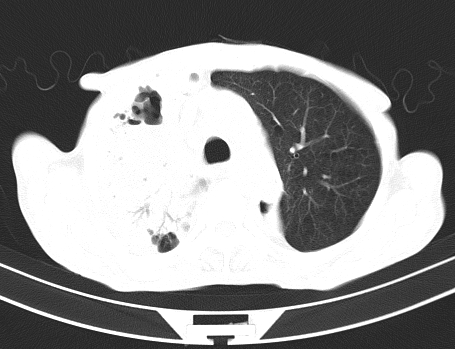

以下是引用gaoshengjiang在2008-5-30 19:53:00的发言:[br]右上叶可见大片实变影,其内可见充气支气管影及囊状影,右上叶尖端支气管走形区可见结节样影,左侧胸腔内可见胸腔胃影。纵隔淋巴结肿大。[br]考虑:1.右上肺阻塞性肺炎伴肺脓肿形成。支持转移所致。[br] 2.左侧胸腔胃。